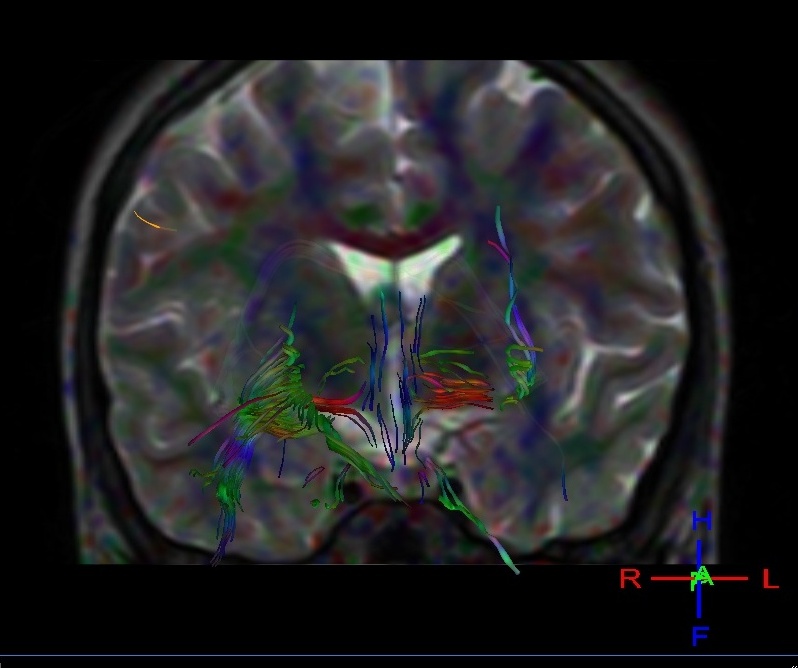

Die Lebersche hereditäre Optikusneuropathie, kurz LHON, ist eine erblich bedingte Mitochondriopathie, die zu einer rasch progredienten Degeneration retinaler Ganglienzellen führt. Eine kausale Therapie ist bis dato nicht verfügbar und während in frühen Stadien der .Die Lebersche hereditäre Optikusneuropathie (LHON) ist die am häufigsten auftretende mitochondriale Erkrankung, und diese vererbte Form des akuten oder subakuten Sehverlusts betrifft vorwiegend junge Männer.Die L ebersche H ereditäre O ptikus- N europathie (kurz LHON) ist eine seltene erbliche Erkrankung, die zu einer massiven Einschränkung des Sehvermögens führt.Lebersche Hereditäre Optikus-Neuropathie (LHON) ist eine seltene, chronisch schädigende mitochondriale Erbkrankheit, die meist innerhalb eines Jahres zu einer ausgeprägten schmerzlosen Visusminderung bzw. Je nach vorliegender Mutation kann es zur spontanen Rückbildung der Symptome kommen.deOptikusneuropathie, Lebersche Hereditäre .